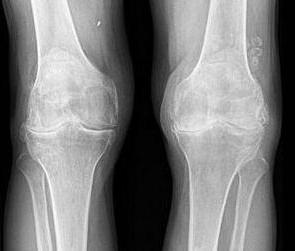

- Рентгенография коленных суставов.

Рентгенографию коленного сустава делают в боковой и прямой проекциях. К рентгенологическим признакам артроза относится: уменьшение высоты суставной щели, костные разрастания, остеофиты, остеосклероз субхондральный, кисты в эпифизах, деформация.

В начальных стадиях развития заболевания, когда еще нет рентгенологических признаков, более информативным методом исследования будет магнитно-резонансная томография (МРТ). Этот метод позволяет увидеть изменения хряща, его истончение, растрескивание, оценить состояние синовиальной оболочки. Из инвазивных методов информативным является артроскопия. Она позволяет визуально осмотреть все внутренние составляющие сустава.